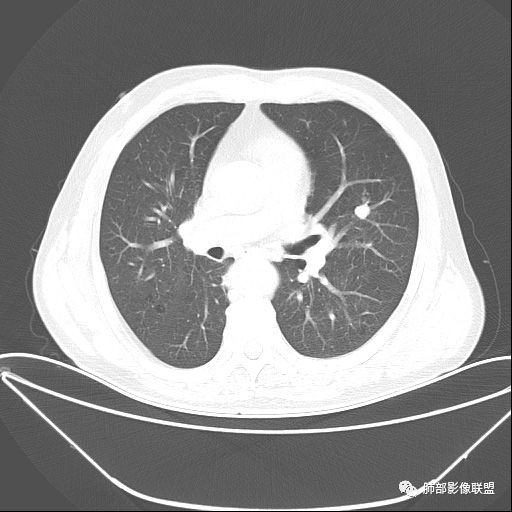

老年男性,两肺可见小叶中央型肺气肿,提示应该有抽烟史。2016年片,右肺门支气管稍模糊,考虑慢性感染,纵膈淋巴结稍大。但2017年左肺上叶新发占位,堵塞支气管,引起局部肺不张伴感染,且纵膈淋巴结较2016年变大,患者同时伴有咯血,考虑恶性。鳞癌?类癌?小细胞?

肺气肿背景,2016年左肺上叶上舌段见微结节,2017年5月左肺结节增大,密度均匀,边缘光滑锐利,与邻近血管关系密切,血管贴壁走行,外侧见尖状突起,下舌段片状影,沿着支气管走行,内有粘液栓,考虑鳞癌,鉴别小细胞肺癌。

肺气肿背景,2016年左肺上叶上舌段见微结节,一年后左肺结节增大,密度均匀,边缘光滑、膨隆,似见小分叶,下舌段片状影,沿着支气管走行,内,老年患者,咯血1月。考虑恶性病变并阻塞性肺炎,鳞癌?注意鉴别结核。

老年男性,咯血1月,肺气肿背景,16年左肺上叶舌段结节,左肺门疑似淋巴结肿大,呈结节感。17年左肺上叶舌段见沿支气管走行分布结节 远端阻塞性肺炎,左肺门淋巴结肿大明显,首先考虑恶性病变,鳞癌?类癌?

前次片2016年4月20相应位置就有小点状病灶,2017-5-15呈结节影改变,边界膨隆,远端阻塞炎性改变,考虑肺癌,鉴别炎性结节!

前后对比,这些结节其实是没引起支气管远端病变的

@南边 关键是上面这几个结节有的密度度,有的密度低。与下面堵塞支气管的结节样改变是否不是一回事,

如果下面堵塞是恶性,那上面的是不是考虑转移?另外一年结那个疑似结节的地方与现在堵塞的地方好象不一致。

后头看前片似乎当时腔内壁稍增厚一点

那就是说这是新发的